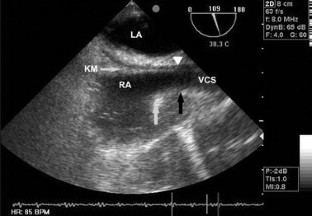

In dieser prospektiven randomisierten Studie wurden bei jeweils 100 Patienten die rechte bzw. die linke V. jugularis interna kanüliert. Die Katheterspitze wurde mithilfe des Elektrokardiogramms (EKG) platziert. Der Katheter wurde an der Stelle fixiert, an der die P-Welle die größte Amplitude erreichte. Die Einführtiefe wurde notiert. Mit Hilfe der TEE wurde die Lage der ZVK-Spitze in Relation zur Crista terminalis bestimmt.

Mithilfe der intraatrialen Elektrokardiographie konnte immer eine maximale P-Welle definiert werden. Alle ZVK-Spitzen lagen innerhalb einer Distanz von ± 0,5 cm zur Basis der Crista terminalis am Übergang der V. cava sup. zum rechten Vorhof. Radiologisch lagen alle Katheter zudem parallel zum Verlauf der V. cava superior.

In this prospective randomized study the right or left internal jugular vein was cannulated with 100 patients in each group and catheter tip positioning was guided by means of ECG. The catheter was fixed at the position of maximum P-wave amplitude and the insertion depth was registered. The relationship of the CVC tip position to the superior edge of the crista terminalis was demonstrated with the help of TEE.

In all patients the catheter tip was found ± 0,5 cm from the superior edge of the crista terminalis at the transition from the superior vena cava to the right atrium. On x-ray control, all catheters ran along the length of the vessel wall of the superior vena cava.